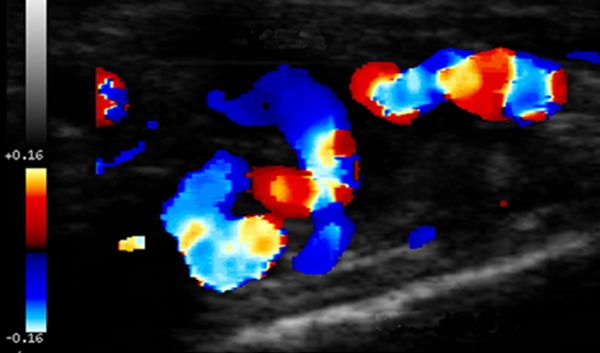

Color-coded duplex ultrasonography shows a massive increased blood flow, but not in multiple, very small reticular vessels as expected in an infantile hemangioma. The vessels were larger. This finding is more consistent with an arteriovenous malformation.